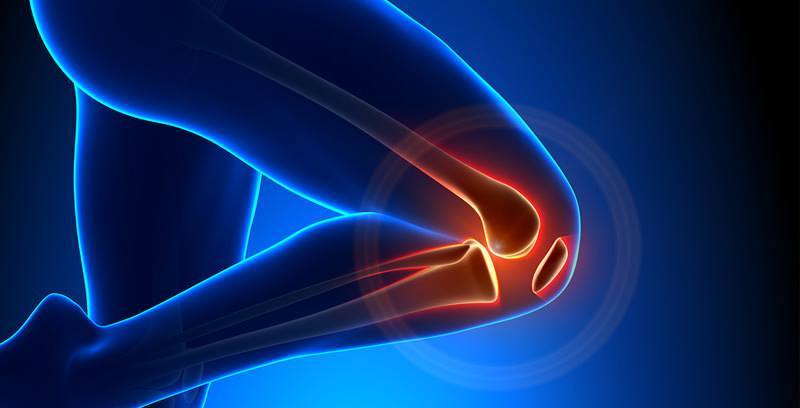

• Mantener un peso adecuado y seguir una dieta saludable le permitirá sentirse más flexible y ágil en el movimiento. Reducirá la carga en las articulaciones de sus extremidades inferiores, principalmente en las rodillas. Y evitará la progresión de la artrosis en pacientes diagnosticados. Es decir, que los huesos protegidos por el menisco dejen de rozar produciendo dolor e inflamación.